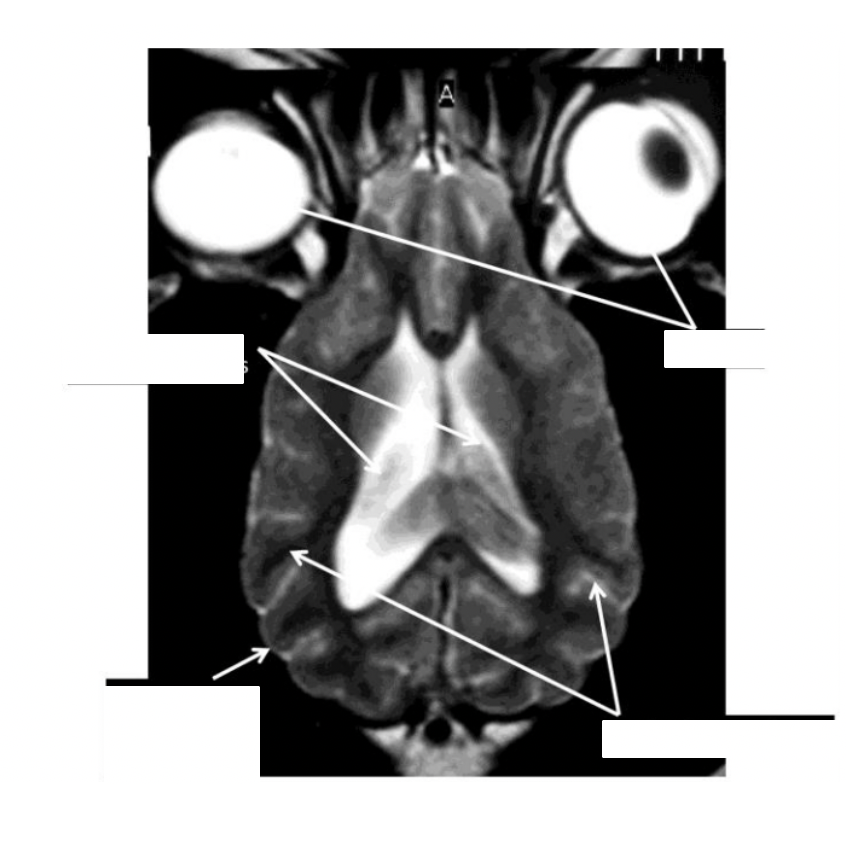

what are the structures shown

identify the structures

what are the species differences between cat and dog (shape, proportional sizes of the cerebral hemispheres and cerebellum)

the lateral ventricles are smaller in cats than in dogs